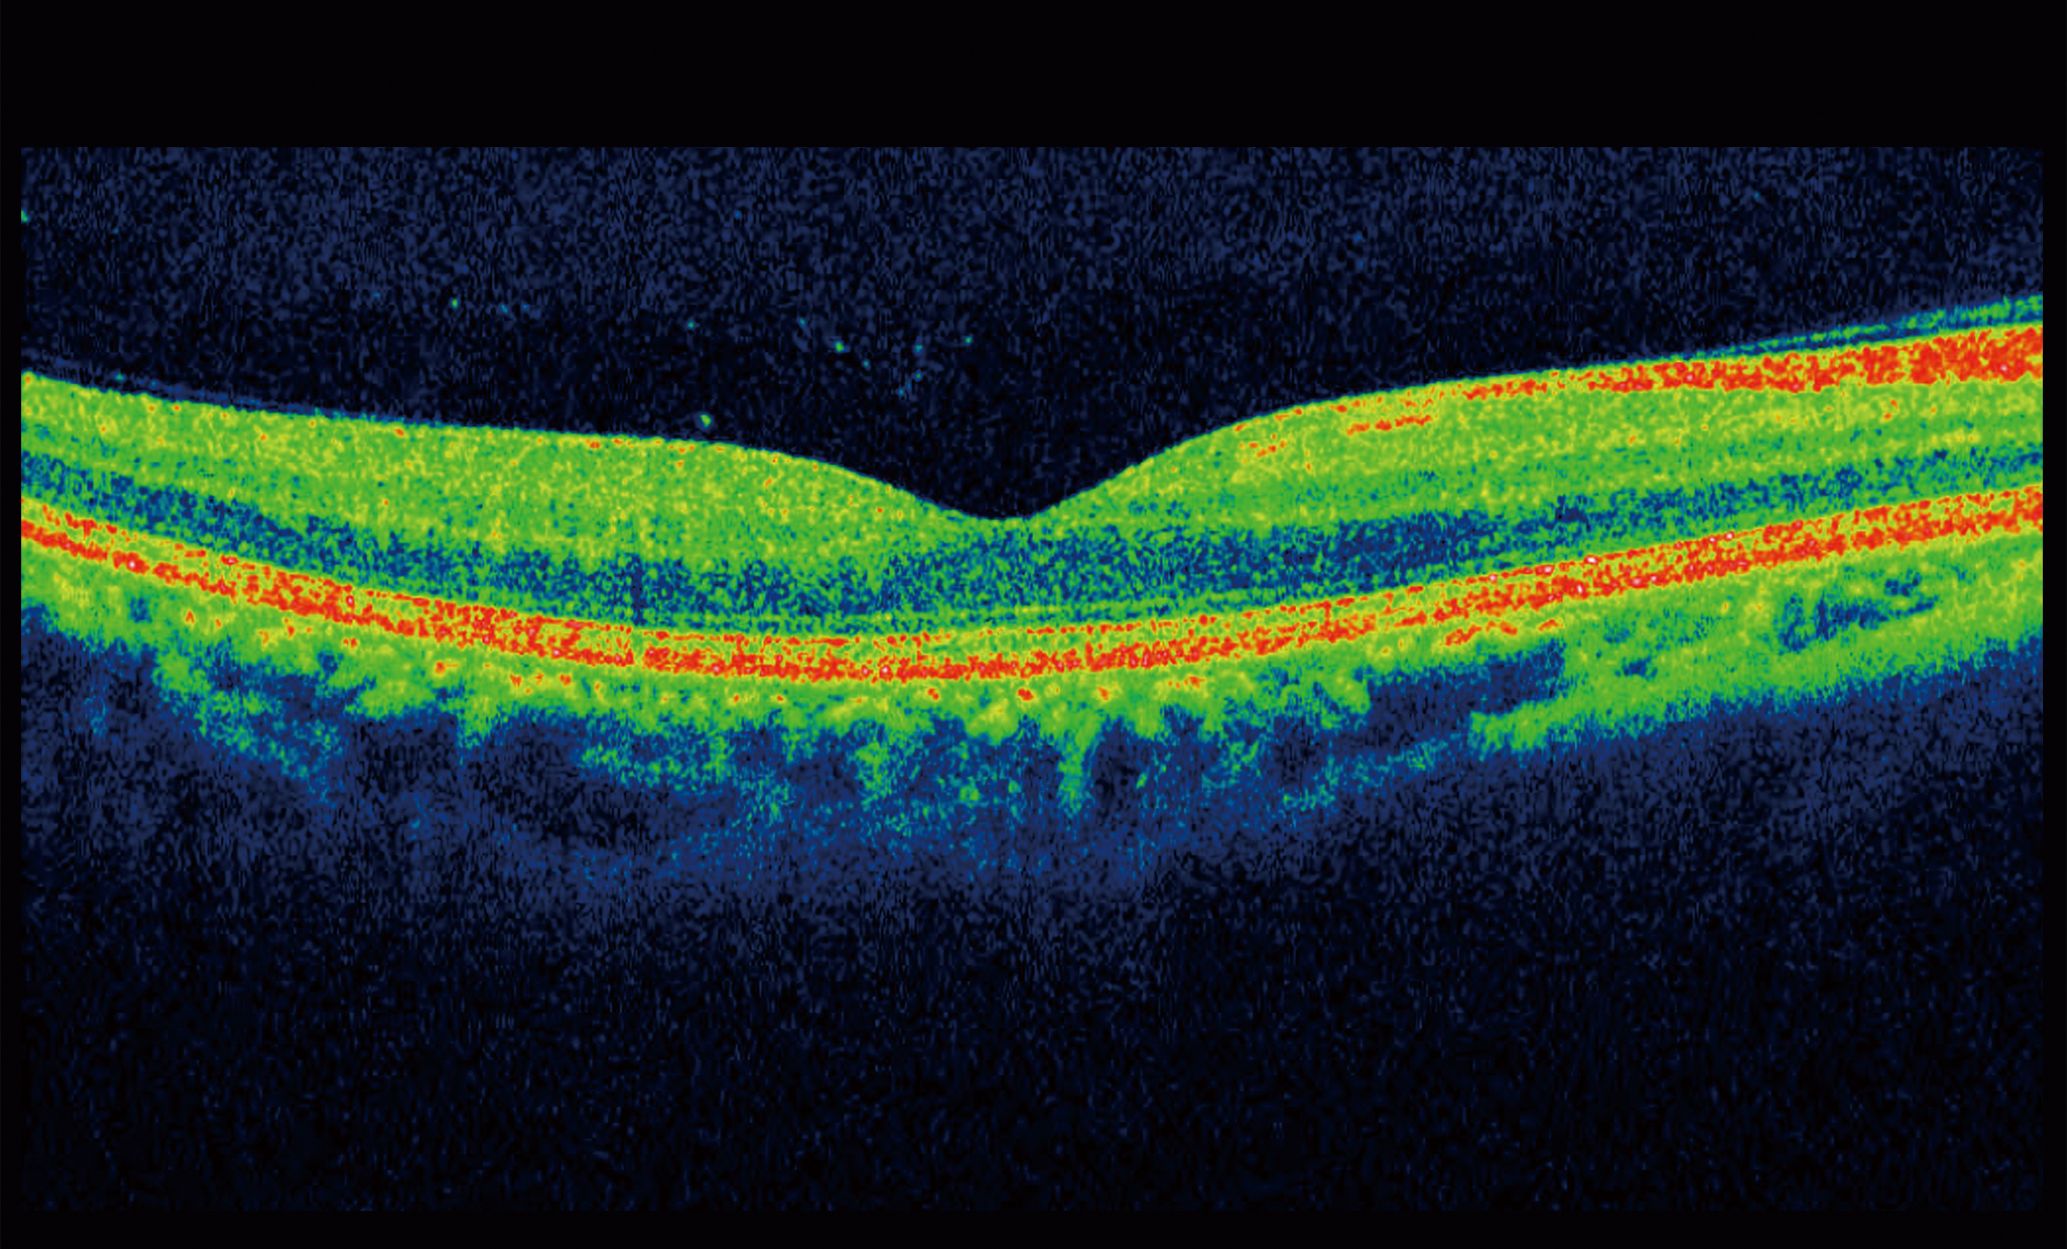

Optical Coherence Tomography

An Optical Coherence Tomography (OCT) scan can scan both the retina, and the optic nerve, it is quick, safe and painless and it shows your optometrist the layers underneath your retina, something that they would not be able to see in anyway in a basic eye test, but can show in detail how healthy your eyes are, and help us to monitor the health of your eyes to find signs of any problems earlier, meaning that we can advise you and if necessary help you to get any necessary treatments.